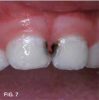

Case 2. This 2-year-old boy had mesial caries lesions of his maxillary central incisors associated with chronic plaque accumulation and lack of tooth brushing or flossing by the parents (Figure 5 and Figure 6). The parents, who were given extensive instructions to remedy the oral hygiene problem, consented to SDF application despite the black discoloration. They related that they not only wanted to avoid a repair appointment for the child, but they also liked the idea that traditional restoration could be delayed until he was older and could more easily tolerate treatment. Three months after initial SDF application, the solution was reapplied (Figure 7).

Fig 7. 3 months after SDF application, before renewed application.

Fig 7